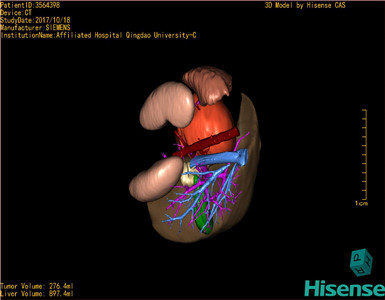

胰腺实性假乳头状瘤-CH-001-N-001499

CT结果输入海信CAS系统后行3D重建及手术规划后,于2017-10-19全麻下行“胰体尾肿物切除术+脾切除术+大网膜切除术”手术治疗:

术前三维重建及手术方案设计:

将0.625mm双源薄层CT资料的静脉期和动脉期Dicom格式文件导入海信CAS系统。

通过调节窗宽窗位调整CT序号,对肝实质,胆囊,下腔静脉,肿瘤,肝动脉、门静脉及肝静脉等进行三维重建;系统自动计算肝脏体积。

模拟手术操作,自动计算切除肿瘤体积。肝脏体积为453.7ml,通过比对2-3岁正常肝脏体积为475.97±99.7ml,通过术前模拟手术,精准判断切除后剩余肝脏体积能耐受,避免肝衰竭发生。

术前三维重建:

重建图片